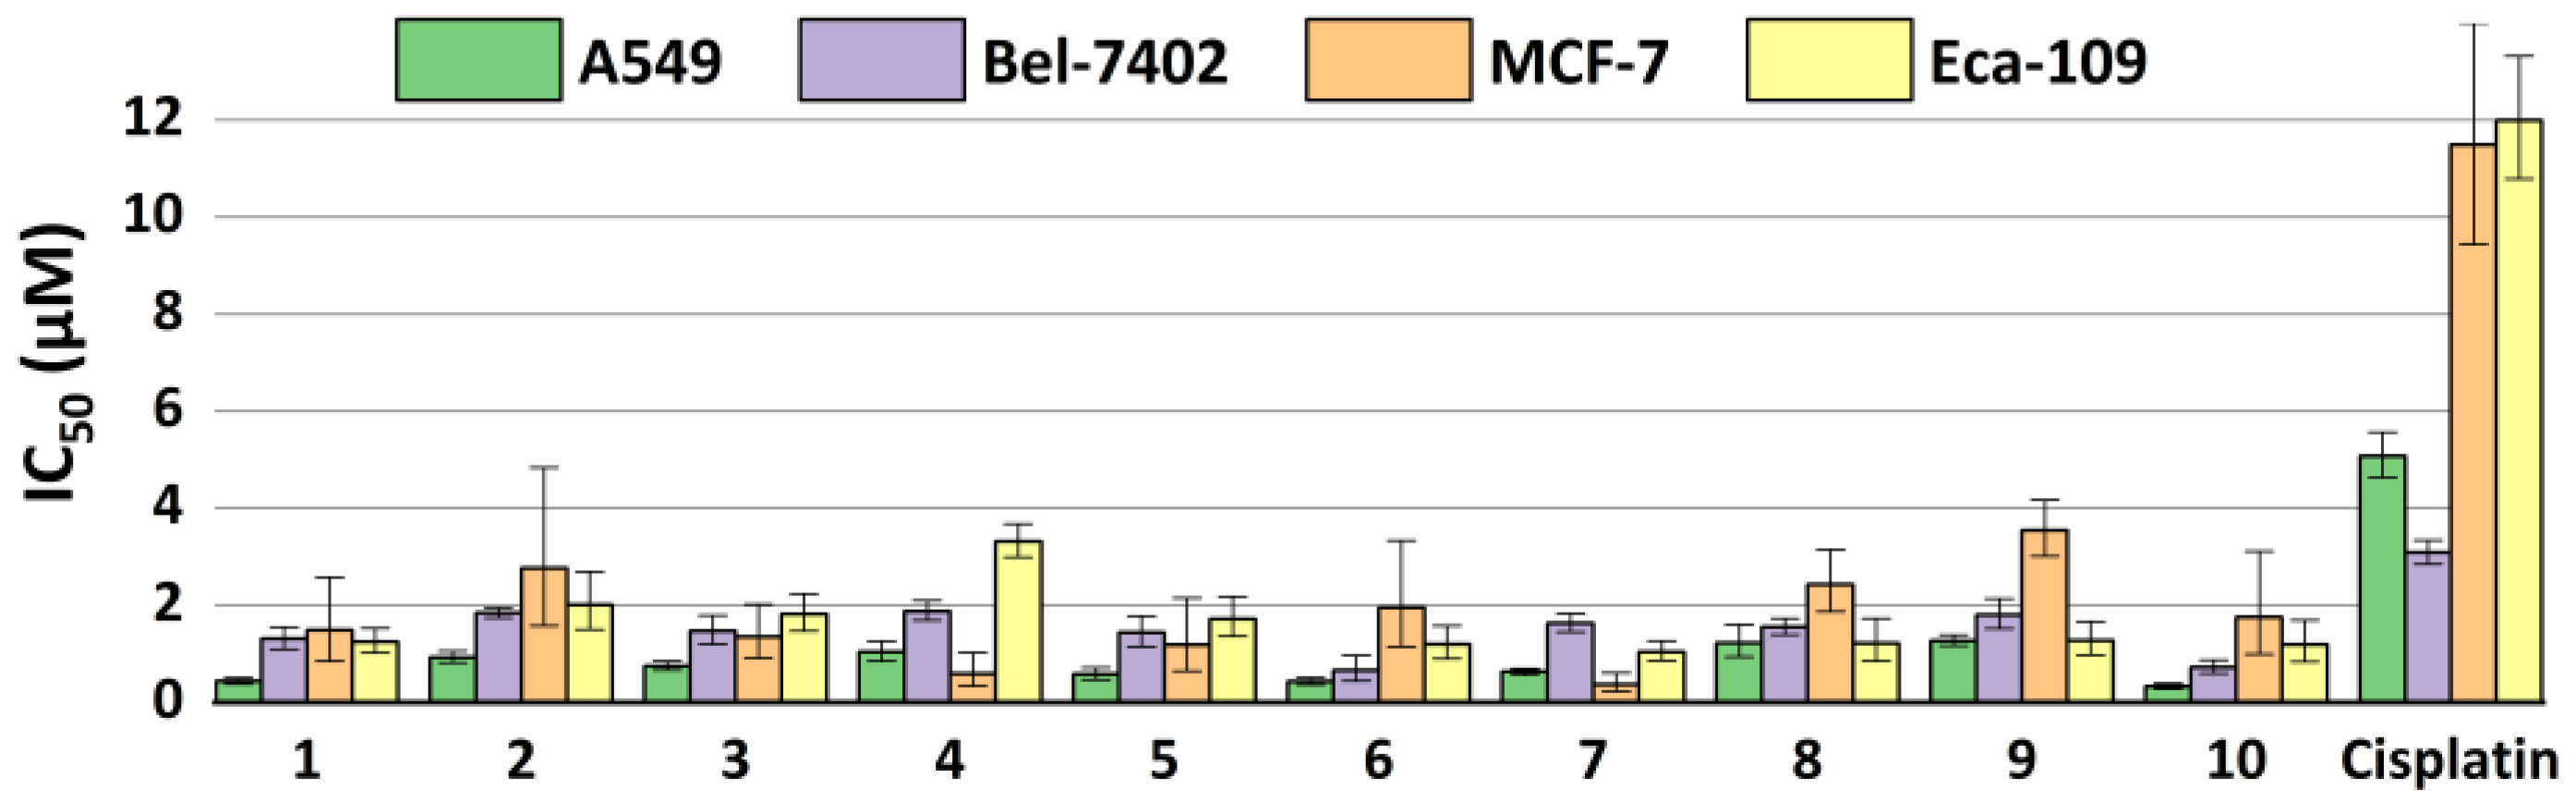

2.5. Antiproliferative Properties

3.6. Antiproliferative Activity In Vitro

| Compound | A549 | Bel-7402 | MCF-7 | Eca-109 | ||||

|---|---|---|---|---|---|---|---|---|

| IC50 (μM) | 95% Confidence Intervals (μM) | IC50 (μM) | 95% Confidence Intervals (μM) | IC50 (μM) | 95% Confidence Intervals (μM) | IC50 (μM) | 95% Confidence Intervals (μM) | |

| 1 | 0.440 | 0.384–0.504 | 1.309 | 1.098–1.560 | 1.486 | 0.855–2.582 | 1.251 | 1.024–1.528 |

| 2 | 0.933 | 0.821–1.061 | 1.842 | 1.741–1.949 | 2.769 | 1.584–4.840 | 2.017 | 1.507–2.701 |

| 3 | 0.756 | 0.672–0.852 | 1.470 | 1.202–1.797 | 1.358 | 0.911–2.025 | 1.821 | 1.475–2.247 |

| 4 | 1.042 | 0.858–1.265 | 1.883 | 1.691–2.096 | 0.589 | 0.336–1.035 | 3.320 | 2.996–3.680 |

| 5 | 0.586 | 0.476–0.722 | 1.435 | 1.150–1.790 | 1.187 | 0.655–2.152 | 1.722 | 1.360–2.181 |

| 6 | 0.435 | 0.370–0.513 | 0.660 | 0.447–0.975 | 1.956 | 1.148–3.332 | 1.198 | 0.908–1.580 |

| 7 | 0.633 | 0.568–0.705 | 1.636 | 1.459–1.835 | 0.374 | 0.229–0.609 | 1.045 | 0.862–1.266 |

| 8 | 1.228 | 0.938–1.608 | 1.557 | 1.396–1.736 | 2.428 | 1.870–3.153 | 1.215 | 0.852–1.732 |

| 9 | 1.270 | 1.165–1.385 | 1.804 | 1.521–2.139 | 3.548 | 3.016–4.173 | 1.280 | 0.985–1.665 |

| 10 | 0.333 | 0.279–0.396 | 0.730 | 0.604–0.883 | 1.764 | 0.999–3.116 | 1.193 | 0.841–1.692 |

| Cisplatin | 5.082 | 4.639–5.568 | 3.088 | 2.856–3.340 | 11.49 | 9.435–14.00 | 11.99 | 10.79–13.32 |